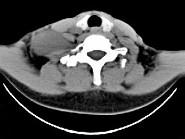

问题 女,47岁,下颈部触及一包块约5年余,CT如图所示,最可能诊断为()

选项 A.滑膜肉瘤 B.血管瘤 C.神经鞘瘤 D.副神经节瘤 E.巨淋巴结增生症

答案 C